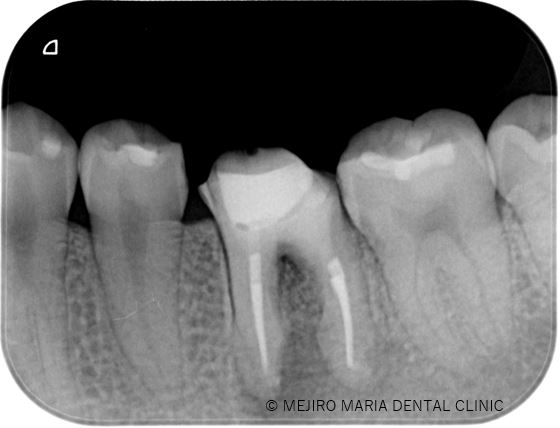

顕微鏡下にて、軟化象牙質(虫歯)や根管内充填物を綺麗に除去し、貼薬を1週間行いました。

1週間後、痛みと腫れは消失しました。